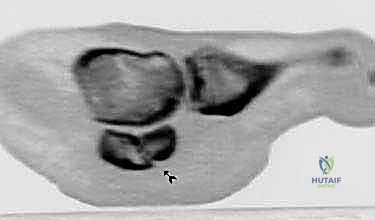

3. التصوير بالرنين المغناطيسي (MRI)

يُعد الرنين المغناطيسي المعيار الذهبي لتشخيص الكسور الإجهادية في مراحلها المبكرة قبل ظهورها في الأشعة السينية. كما يكشف عن وذمة نخاع العظم (Bone Marrow Edema)، وتمزق الأوتار المحيطة، وتلف الغضاريف.

4. التصوير المقطعي المحوسب (CT Scan)

في الحالات المعقدة التي يخطط فيها الدكتور للتدخل الجراحي، يوفر التصوير المقطعي صوراً ثلاثية الأبعاد تفصل حجم الكسر، وعدد الشظايا العظمية، ومدى تباعدها، مما يساعد في وضع خطة التثبيت الداخلي بمنتهى الدقة.